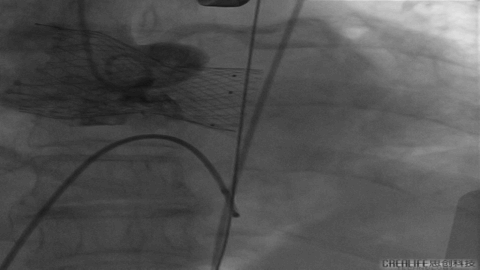

Nmued20预扩1

Nmued20预扩2